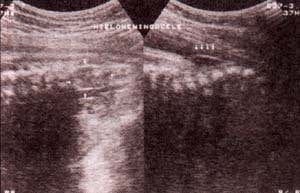

fig. 85. – (a). mielomeningocele lumbosacro. 30 semanas. hidrocefalia asociada. |

fig. 85. – (b). corte coronal. se observa la separación anormal de las apófisis vertebrales por la presencia de la masa de tejido neural

fig. 85. – (c). corte longitudinal. la proyección lateral permite observar la masa protruyendo no cubierta por piel. |

fig. 86. – (a). Meningocele Lumbosacro extenso. 34 semanas. corte sagital. gran defecto lumbosacro. Se observan las meninges expuestas sin piel recubriendo el área. |

fig. 86. – (b). corte transversal . imagen en “v” característica secundaria a la separación anormal de las apófisis transversas permitiendo la herniación de las meninges |